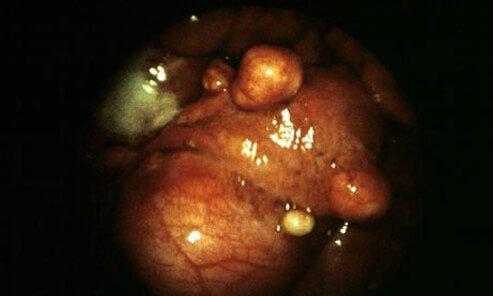

text_fieldsബംഗളൂരു: ബംഗളൂരുവിൽ 34കാരിയുടെ ഗർഭപാത്രത്തിൽനിന്നും 222 മുഴകൾ (ഫൈബ്രോയിഡ്സ്) ശസ്ത്രക്രിയയിലൂടെ വിജയകരമായി നീക്കം ചെയ്തു. ബംഗളൂരു സക്ര വേൾഡ് ആശുപത്രിയിലെ ഡോക്ടർമാരാണ് ഇത്രയധികം മുഴകൾ സങ്കീർണമായ ശസ്ത്രക്രിയയിലൂടെ നീക്കിയത്. ഗർഭപാത്രത്തിൽ മുഴകൾ ഉള്ളതുകൊണ്ട് അസാധാരണമായ ആർത്തവ രക്തസ്രാവവുമായാണ് മീഡിയ പ്രഫഷനലായ റിതിക എന്ന 34കാരി ആശുപത്രിയിൽ ചികിത്സ തേടിയത്.

വിളർച്ച, ക്ഷീണം, അടിവയറിന് വേദന തുടങ്ങിയ അസ്വസ്ഥതകളായിരുന്നു ഉണ്ടായിരുന്നത്. ഗർഭാശയത്തിെൻറ ഘടന തന്നെ വികലമാക്കുന്ന മുഴകൾ നാലര മണിക്കൂർ നീണ്ടുനിന്ന ശസ്ത്രക്രിയയിലൂടെയാണ് നീക്കം ചെയ്തത്. പരിശോധനയിൽ യുവതിയുടെ ഗർഭ പാത്രം എകദേശം എട്ടുമാസം ഗർഭം ധരിച്ചതിെൻറ അത്രയും വലുപ്പത്തിലാണുണ്ടായിരുന്നതെന്നും അടിവയറ്റിൽ വീക്കമുണ്ടായിരുന്നതായും സക്ര ആശുപത്രിയിലെ സീനിയർ കൺസൾട്ടൻറും ഗൈനോക്കാളജി മേധാവിയുമായ ഡോ. ശാന്തല തുപ്പണ്ണ പറഞ്ഞു.

പല വലുപ്പത്തിലുള്ള 222 മുഴകൾ ചേർന്ന് ആകെ 2.2 കിലോയോളം ഭാരമാണുണ്ടായിരുന്നത്. മൂത്രസഞ്ചിയിലും ഗർഭപാത്രത്തിെൻറ ഇടതുഭാഗത്തുമാണ് മുഴകളുണ്ടായിരുന്നത്. 50ശതമാനം വരെ സ്ത്രീകളിൽ ഗർഭായ മുഴകൾ സാധാരണമാണ്. എന്നാൽ, ഇത്രയധികം മുഴകൾ അപൂർവമാണ്. കോവിഡിനെതുടർന്ന് ഒരു വർഷത്തോളം ഗർഭപാത്രത്തിലെ മുഴക്ക് ചികിത്സ തേടാനും വൈകിയിരുന്നു. അർബുദമായി മാറില്ലെങ്കിലും ഇത്തരം മുഴകൾ നീക്കം ചെയ്തില്ലെങ്കിൽ മറ്റു ആരോഗ്യപ്രശ്നങ്ങൾക്ക് ഇടയാക്കും.